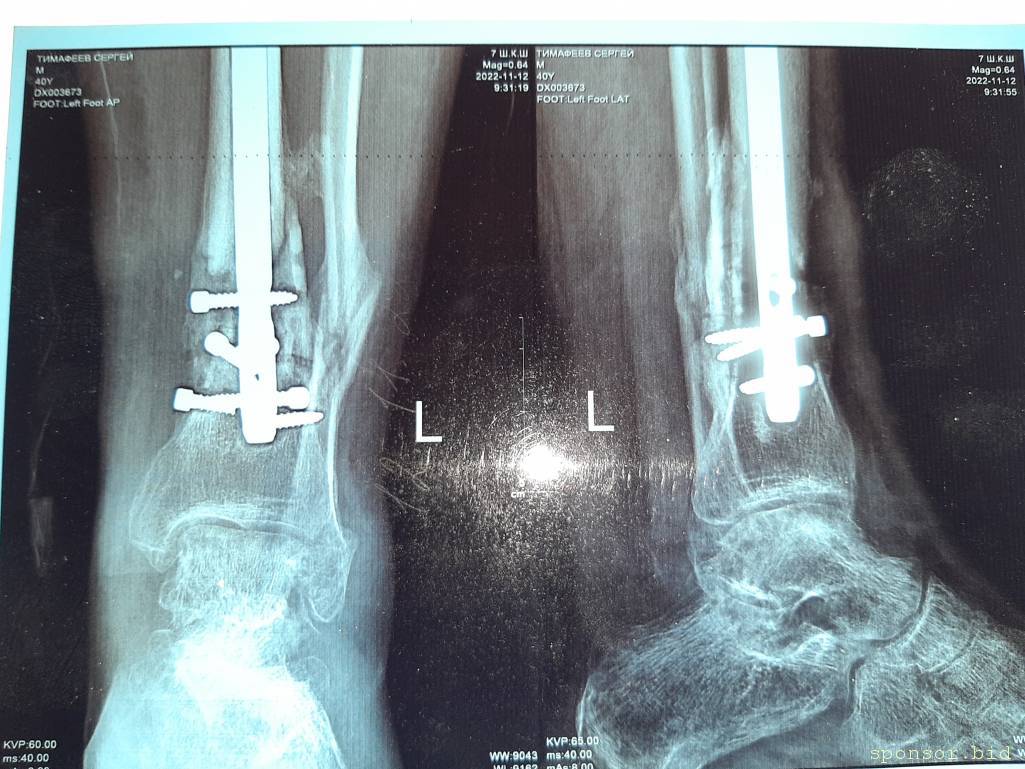

Вот что со мной произошло: летом прошлого 2022 года я неудачно упал, и сломал левую ногу, да так, что всё не закончлось просто гипсом. Перелом был сложным, пришлось делать операцию, ставить биос. Операция прошла с осложнениями, был свищ, нога после операции долго не заживала. Потом сломался крепёжный саморез, стало ещё хуже. Заболела правая нога в колене и бёдре. На приёме у врача сказали нужна операция! И в ближайшее время! Но я на больничном уже целый год, и после такого продолжительного лечения, все мои финансы на нуле. Ходить не могу, спать не могу, мучают постоянные боли. У меня развился сахарный диабет, ноги болят, появилась венозная недостаточность и варикоз. Мне всего 41 год. Получается я останусь инвалидом навсегда... Но у меня есть двое детей 5 и 14 лет... В данный момент я не могу встать на ноги из-за отсутствия финансовых средств. Моя мама Лариса Андреевна, помогает мне по мере своих сил. Ей приходится работать на производстве. Но ей уже 75 лет...

Нужна помощь сыну сотрудницы Не может ходить. - 20230719_135402.jpg

Нужна помощь сыну сотрудницы Не может ходить. - 20230719_135435.jpg